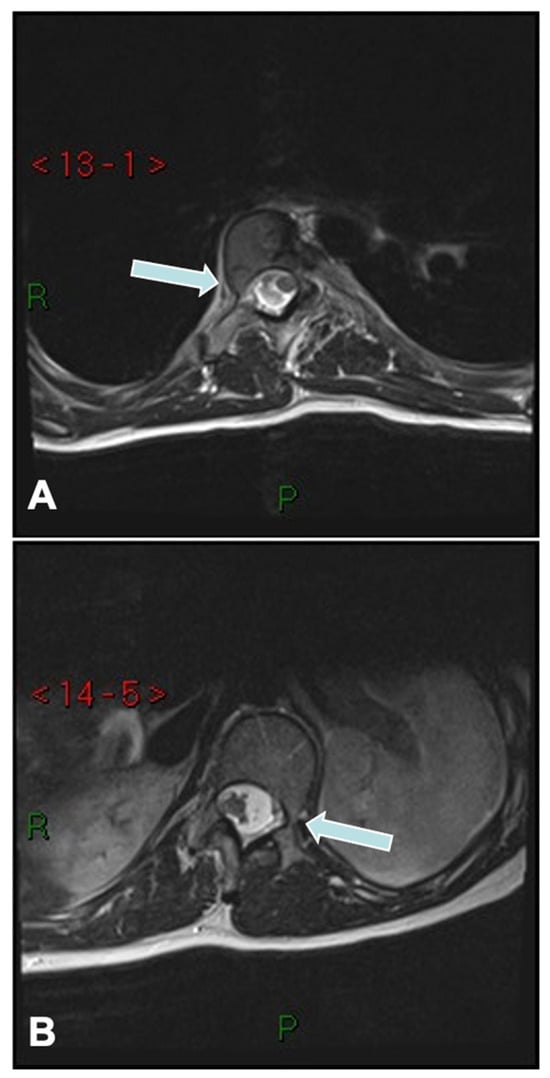

The convex pedicle screw technique in AIS, developed by Tsirikos, is a novel approach that introduced segmental correction through instrumentation and maneuvers applied on the convex side of the spinal deformity. Unlike traditional techniques focusing on concave rod engagement, this method prioritizes convex-side anchoring for improved coronal and sagittal alignment while minimizing neurological and vascular risks. The rationale for using the convex rod technique is based on several advantages, including a lower risk of neurological injury due to the reduced likelihood of medial pedicle breach (Figure 4), as well as the ability to use larger and longer pedicle screws on the convex side, which provide superior purchase and stability. Additionally, this technique facilitates improved coronal plane correction while simultaneously restoring thoracic kyphosis, which is often reduced in AIS. Another key benefit is the use of a lower implant density that reduces surgical time, blood loss, and infection risks while still achieving very satisfactory deformity correction.

The surgical procedure begins with preoperative planning using full-length standing and supine traction scoliosis radiographs complimented by a whole-spine MRI to assess curve flexibility and three-dimensional alignment. This technique can be used for any Lenke type of AIS. The patient is positioned prone on a Jackson table using a Montreal mattress to facilitate spinal alignment and a midline posterior exposure is performed, followed by subperiosteal dissection to the tips of the transverse processes. Facetectomies are routinely performed to increase segmental flexibility, which is essential for optimal correction. Pedicle screws are then placed segmentally on the convex side to allow controlled vertebral translation and coupled derotation, while only two proximal and distal screws are placed on the concave side, in order to augment the construct and provide additional stabilization.

The convex rod, which is pre-contoured to restore normal sagittal alignment, is engaged sequentially in the segmental screws. The key initial corrective maneuver involves segmental vertebral translation, where the vertebrae are gradually pulled toward the rod using reduction screws. Direct vertebral derotation is then applied at every level as the convex pedicle screws are locked into the monoaxial screws, further improving the axial deformity. A concave rod is placed once the correction is achieved and the convex rod has been secured to the spine, but its role is primarily supportive rather than corrective. The final step involves the final tightening of the screws on the rods with controlled compression and distraction at the caudal and cephalad ends in order to optimize spinal balance, followed by bone grafting using locally harvested bone and allograft, as needed, to promote fusion. A case example is shown in Figure 5.